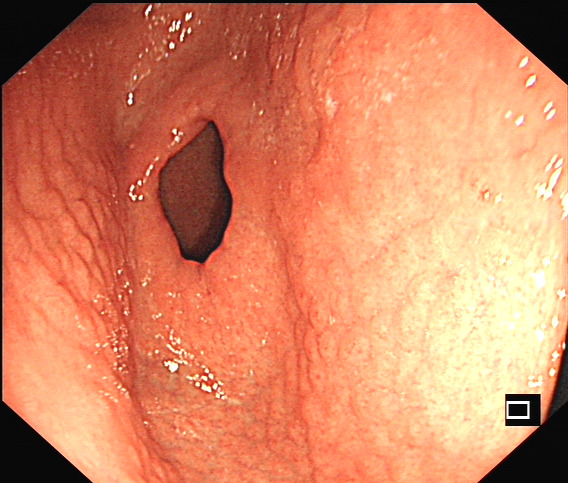

幽门螺旋杆菌感染临床上颇为常见,本次查看体检结果,发现一个“珍珠胃”的,其实就是胃窦结节样改变,这个是幽门螺旋杆菌感染内镜下最典型的一个表现了,其他的还有粘膜发红充血、息肉等,相对来说缺乏一些特异性。

幽门螺旋杆菌感染相关胃炎胃镜下表现